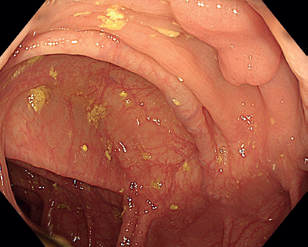

Obr. 4 Stopka polypu po endoskopické polypektomii v bílém světle.Endoskopická slizniční resekce (EMR) je specializovanou technikou pro odstranění povrchových gastrointestinálních lézí, vyvinutou v 50. letech pro sigmoideoskopii a později rozšířenou na kolonoskopii, a nakonec na celý trávicí trakt. Zejména u plochých lézí je výhodné označení okrajů koagulačními body k zajištění odstranění celé léze. Využívá se zejména pro léze větší než 10 mm, které nejsou vhodné pro klasickou polypektomii. Principem EMR je vytvoření pseudopolypu z nepolypoidní léze, což umožňuje lézi zachytit a odstranit pomocí polypektomické kličky.